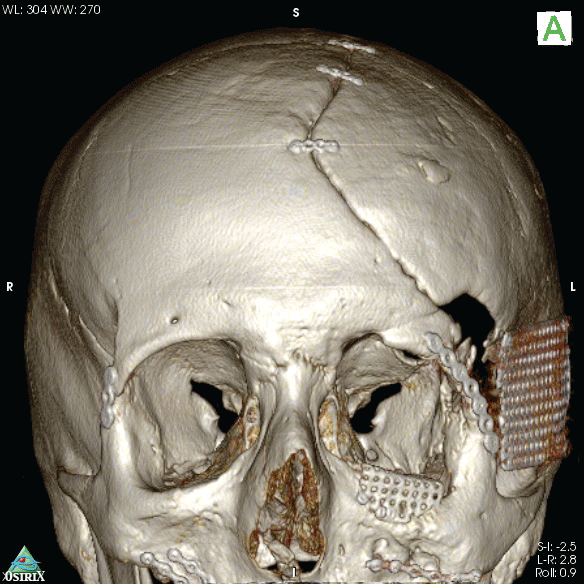

Due to a high-energy motorcycle accident, a male 21 year-old patient suffered frontal anterior cranial vault injuries and skull and pan-facial fractures. He was hospitalized at the local trauma centre and an immediate emergency neurosurgical intervention was performed to reduce the high intracranial pressure level, temporarily removing part of the left parietal and temporal bones and definitively the more comminuted bone fragments from the left orbital rim and roof. When stabilized, a second surgical intervention was performed to practice the cranioplasty, reapplying the previously removed cranial vault bones and to reduce the frontal bone and zygomatic fractures; supraorbital rim comminuted fracture was reconstructed with homologous cadaveric frozen bone; orbital floor defect was sealed with Ethisorb® Dura Patch membrane and the maxillo-zygomatic process was reduced on the left side. Reduction of frontal bone and zygomatic fracture, orbital floor and medial orbital wall reconstruction were also performed on the right side. Despite the treatment, ocular dystopia and severe mid-facial asymmetry with left orbital deformity remained due to the lack of the left orbital floor bone and the presence of still wide missing bone defects (Figure1).

Figure 2: CT 3D rendering after first surgical stage showing the orbital floor defect, mid-facial asymmetry and orbital deformity

The patient's anatomy was then assessed in multiplanar (axial, coronal, sagittal) and 3D computed tomography via Toshiba Aquilon One Helical CT scanner (Figure 2), gantry = 0, slice = 1mm. The orbital floor malposition on the left side was, as measured through the CT images, 7.4 mm caudal than the contralateral one (Figure 3), causing ocular dystopia. DICOM files were processed by DeVIDE software to a .stl file. Then Netfabb software was used to obtain an ABS polymeric stereolithographic model via HP Designjet 3D printer (Figure 4). A silicon impression material was manually adapted on the stereolithopraphic model defective orbital floor to achieve a steam sterilizable autoclavable mould as a helping device in manual bone graft modelling during the surgery.